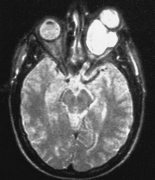

冠狀位t1加權(quán)MRI顯示一個(gè)大的眶內(nèi)腫塊(箭頭)以視神經(jīng)為中心。圖示:46歲男性軸向t2加權(quán)MRI顯示丘腦外側(cè)膝狀核腫塊,起因于患者已知視神經(jīng)膠質(zhì)瘤的連續(xù)延伸。雖然MRI可以發(fā)現(xiàn)視神經(jīng)的...